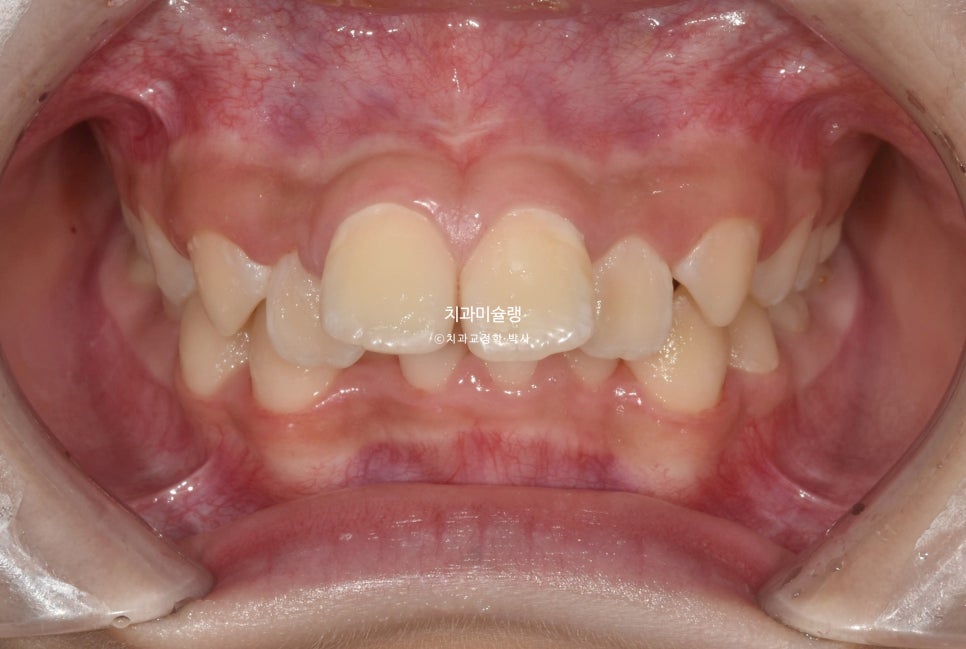

2023년 7월,

앞니 돌출과 삐뚤한 치아 때문에

교정치료를 위해 온 어린이 입니다.

아래앞니가 윗니에 가려 안보일 정도의 심한 과개교합입니다.

앞니가 튀어나온 돌출입니다.

좌우 교합관계가 모두 2급이며 특히 좌측이 더 심합니다.

아랫니도 삐뚤삐뚤 합니다.

유치가 남아있고 나이가 11세 미만이라 인비절라인퍼스트 어린이교정이 가능한 상황 입니다.